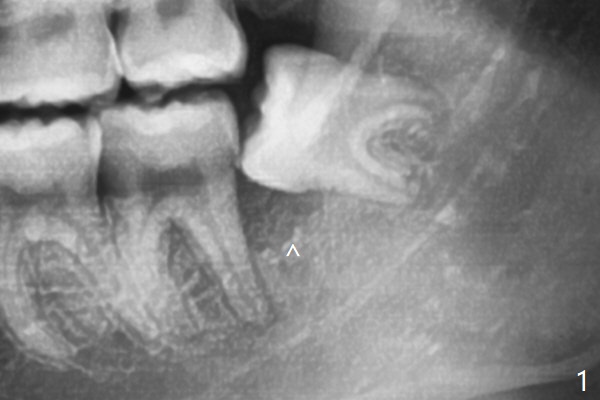

White outline is the orientation (horizontal) and relative position (as mesial as possible) of the Osteogen plug.  One end happens to have been cut.